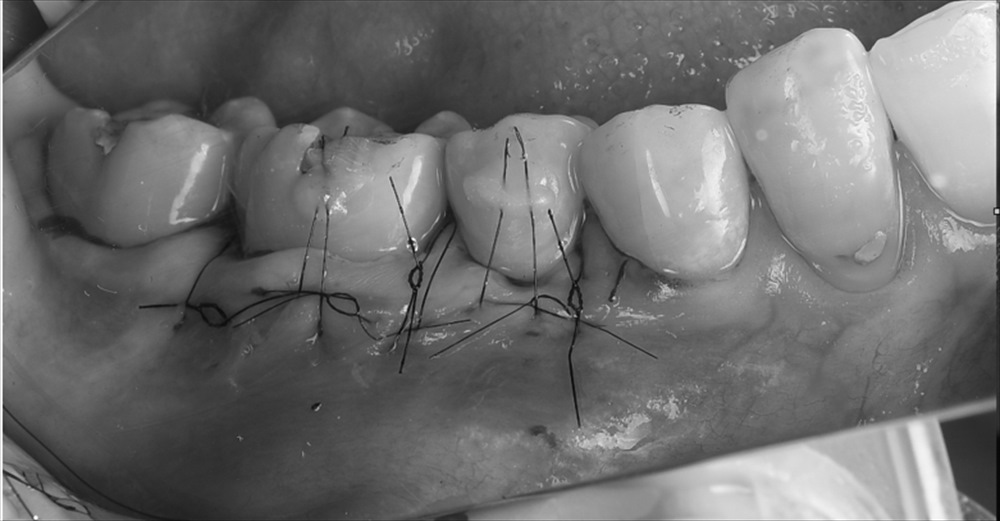

ミラーの分類、タイプ1、カイロの分類ではRT1でした。これを元に根面被覆が可能と判断しマイクロサージェリーを行いました。

歯肉を移植を行い

エンベローブ切開ですので術後も痛くありません。